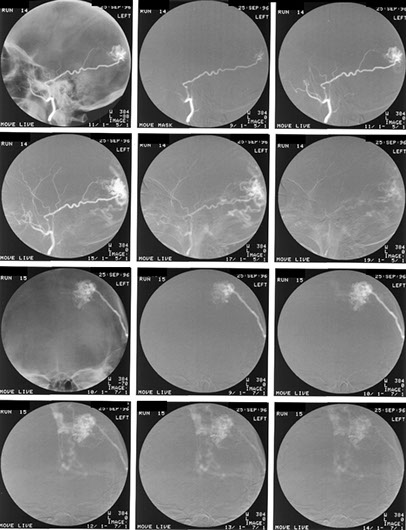

Thrombolysis can be performed on recently thrombosed sections due to embolic disease or focal narrowing by atheroma.

This is the image 8 hours post commencement of thrombolysis.